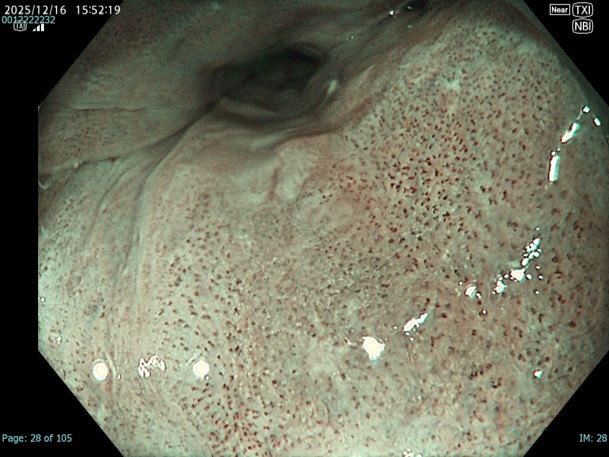

• NBI観察(近景)

強調設定:A8

図3 図4 図5

近景、拡大観察を行う事でIPCLとしては口径不同を伴ったB1血管を診断できる。一方で部位によってはA血管と判別が難しい部位もあり、また色調変化も周囲粘膜とモザイク様で判断が難しい部位も存在する。

• NBI+TXI観察(近景)

切替前 NBI強調設定:A8

NBI+TXIレベル:高

図8 図7 図9

NBI観察と比較するとDLが明瞭であり、この後行うESDにおいてもマーキングに有用であった。